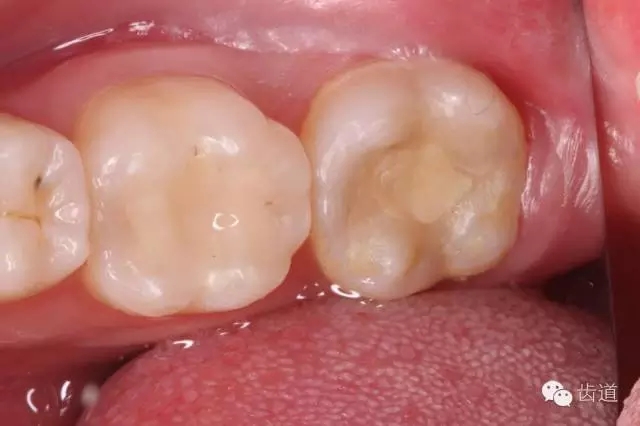

口外檢查: 面部對稱,無腫脹 口內(nèi)檢查: 36合面樹脂樣材料充填,邊緣密合,牙體及修復(fù)材料表面均未見明顯缺損及裂紋,未探及繼發(fā)齲,探痛-,叩痛-,松動-,冷水刺激痛-,未探及牙周袋及附著喪失,牙齦無紅腫,電活力測試平均值為15;37合面樹脂樣材料充填,邊緣密合,牙體及修復(fù)材料表面均未見明顯裂紋,未探及繼發(fā)齲,探痛-,叩痛+++,松動-,冷水刺激痛-,未探及牙周袋及附著喪失,牙齦無紅腫,電活力測試無反應(yīng);38埋伏阻生,可探及齦下牙冠,探痛-,牙齦無紅腫。 26、27牙體未見明顯充填物、缺損、齲壞及裂紋,探痛-,叩痛-,松動-,冷水刺激痛-,未探及牙周袋及附著喪失,牙齦無紅腫; 影像學(xué)檢查: 全景片及X線根尖片顯示36合面充填物影像,靠近髓腔,未見根折影像,未見牙槽骨吸收,未見根分叉透射影,未見根尖周暗影;37合面充填物影像,靠近髓腔,未見根折影像,未見牙槽骨吸收,未見根分叉透射影,根管影像清晰,根中上三分之二粗大,根尖三分一分為近遠(yuǎn)中兩根管,形態(tài)均呈弧形,根尖周膜連續(xù)性中斷,根尖周透射影明顯,進(jìn)一步測量顯示:髓室頂最低點到髓底的距離a,與髓室頂最低點到根尖孔的距離b,兩者關(guān)系為a/b>0.2;38近中阻生,牙根尚未發(fā)育完全,未見冠周明顯透射影像;。CBCT片顯示:在水平斷層上,可見37根管在根尖三分之一為彎曲偏向頰側(cè)的C型,存在近遠(yuǎn)中兩個主根管,中間峽部相連;在矢狀斷層上,可見37根管遠(yuǎn)中根尖孔擴大,遠(yuǎn)中根尖狹窄處位于離解剖根尖約1mm處

2. 術(shù)前X片

可見37根管影像清晰,根中上三分之二粗大,根尖三分一分為近遠(yuǎn)中兩根管,形態(tài)均呈弧形,根尖周膜連續(xù)性中斷,根尖周透射影明顯